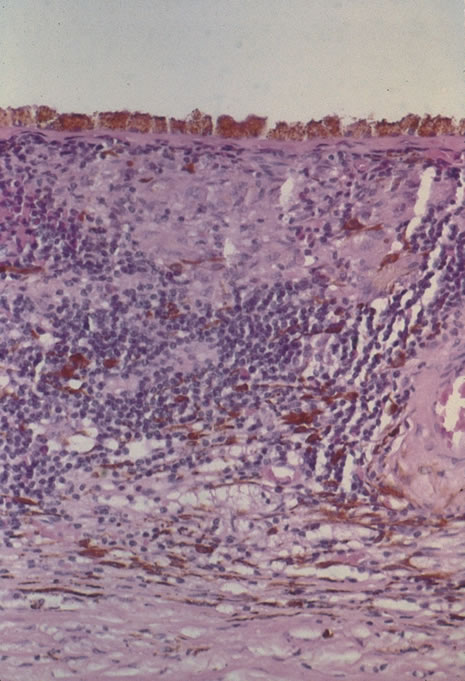

Rubella infections that occur early in gestation are associated with the greatest risk of fetal damage, however, infection in the third trimester may still cause damage. Maternal infection in the first 2 months of pregnancy results in a 40% to 60% chance of multiple congenital anomalies or fetal death. Congenital heart disease, cataracts, and deafness are the classic triad of the congenital rubella syndrome; however, there are many other commonly recognized complications of prenatal rubella infection (Fig. 13). Encephalitis, microcephaly, mental retardation, intrauterine growth retardation, thrombocytopenic purpura, hepatosplenomegaly, obstructive jaundice, interstitial pneumonitis, myocarditis, and radiolucent bone lesions are all possible sequelae of congenital rubella infection.54 The classic salt-and-pepper retinopathy occurs less commonly (Fig. 14), but may be noted to show progression. Other ocular findings include congenital cataracts, microphthalmia and glaucoma. Ocular disease and hearing loss frequently occur together, and glaucoma is frequently associated with microphthalmos.56

|

|